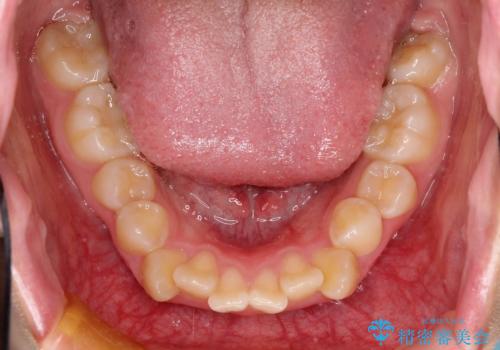

- 上下左右4本の小臼歯を抜歯、ラビアル・ワイヤー矯正を計画した。

抜歯をして第1小臼歯分のスペースを獲得することにより、ガタつきの改善と前歯のリトラクトをおこない、横顔の印象もすっきりとし、整ったEラインを作ることができました。